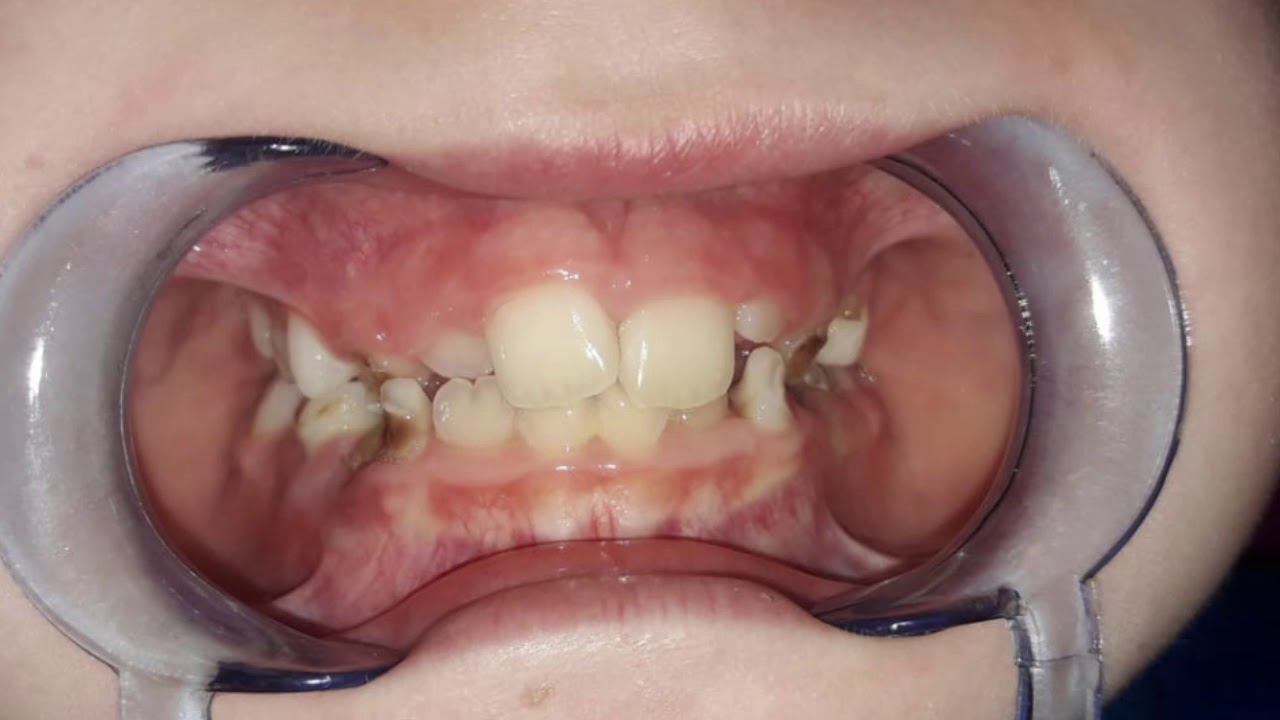

Stosowane są najczęściej u dzieci w okresie wymiany uzębienia, oraz u osób z niewielkimi wadami zgryzu . Projektowane i wykonywane są indywidualnie dla każdego pacjenta. Płytka aparatu w ulubionym kolorze, barwą ulubionego klubu piłkarskiego przypadną do gustu nawet najbardziej wymagającym małym pacjentom. Aparaty te często niesłusznie traktowane są jako gorsze niż aparaty stałe – dość powszechna jest opinia, że należy je nosić tylko w nocy, że dzieci ich nie chcą nosić oraz, że i tak na koniec konieczny będzie aparat stały. W rzeczywistości aparaty zdejmowane nie są zamiennikiem aparatów stałych, a ich uzupełnieniem. Często zaleca się ich stosowanie w pierwszym etapie leczenia, gdy nie ma jeszcze możliwości zastosowania aparatu stałego z powodu trwającej wymiany uzębienia, ale jednocześnie młody wiek pacjenta umożliwia działanie ortopedyczne np. poszerzenie łuku zębowego by w przyszłości uniknąć konieczności usuwania stałych zębów z powodu stłoczeń.